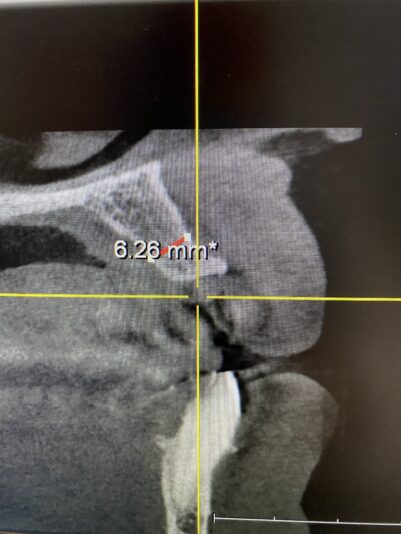

• This case I posted last year when I was planning. Here it is at 5 months, I am concerned about the buccal plate width at the mid/apical third. Clearly should have put this more lingual. Long term predictability?